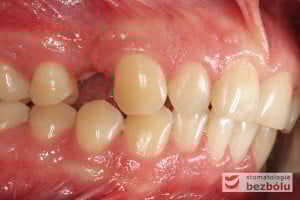

Młody pacjent w wieku lat 28 po wstępnym rozpoznaniu, ze zdiagnozowanym złamaniem kła zarówno górnego jak i dolnego, został skierowany na terapię implantoprotetyczną, prowadzoną przez lekarza dentystę Marcina. W świetle braku możliwości wykonania ekstruzji ortodontycznej i zachowawczego podejścia do leczenia, podjęto decyzję o usunięciu obu zębów, zastosowaniu ułatwiającej gojenie procedury A-PRF i przygotowaniu pacjenta do zabiegu implantologicznego, dodatkowo uzupełnionego o wprowadzenia implantu w miejscu braku zębowego w pEdytujozycji pierwszego przedtrzonowca w szczęce po stronie prawej.

Po zakończeniu procesu gojenia wyrostka zębodołowego, wykonano diagnostykę radiologiczną z zastosowaniem tomografii wiązki stożkowej (CBCT) w celu oceny ilości oraz jakości tkanki kostnej, zarówno w miejscach poekstrakcyjnych, jaki i w pozycji górnego prawego przedtrzonowca. Ponadto pobrano wyciski, oddające sytuację kliniczną w jamie ustnej pacjenta, który zdecydował się na metodę implantacyjną, wykorzystującą nawigację komputerową, z zastosowaniem protokołu MGuide firmy MIS. Procedura ta polega na cyfrowym zaplanowaniu pozycji implantów, a następnie wykonaniu w technice druku 3D szablonu chirurgicznego.Taka metoda pozwala wyeliminować konieczność odwarstwiania płatów, zmniejszając przy tym pozabiegowe dolegliwości. Usprawnia jednocześnie pracę operatora, dokładnie pozycjonując wszczep w pożądanej pozycji. Kolejnym krokiem było przesłanie skanów modeli gipsowych oraz tomografii do siedziby MCenter w Berlinie, gdzie wysoko wyspecjalizowani technicy, dysponujący najnowszą technologią cyfrową, precyzyjnie wykonali szablony nawigacyjne, stosowane podczas zabiegu implantologicznego.